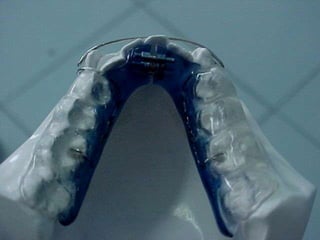

O documento descreve um caso de apinhamento dentário tratado sem extrações. O paciente apresentava asma, respiração bucal e língua hipotônica devido ao apinhamento. O tratamento envolveu remodelação dos dentes sem extrair nenhum, corrigindo o desvio de linha média.